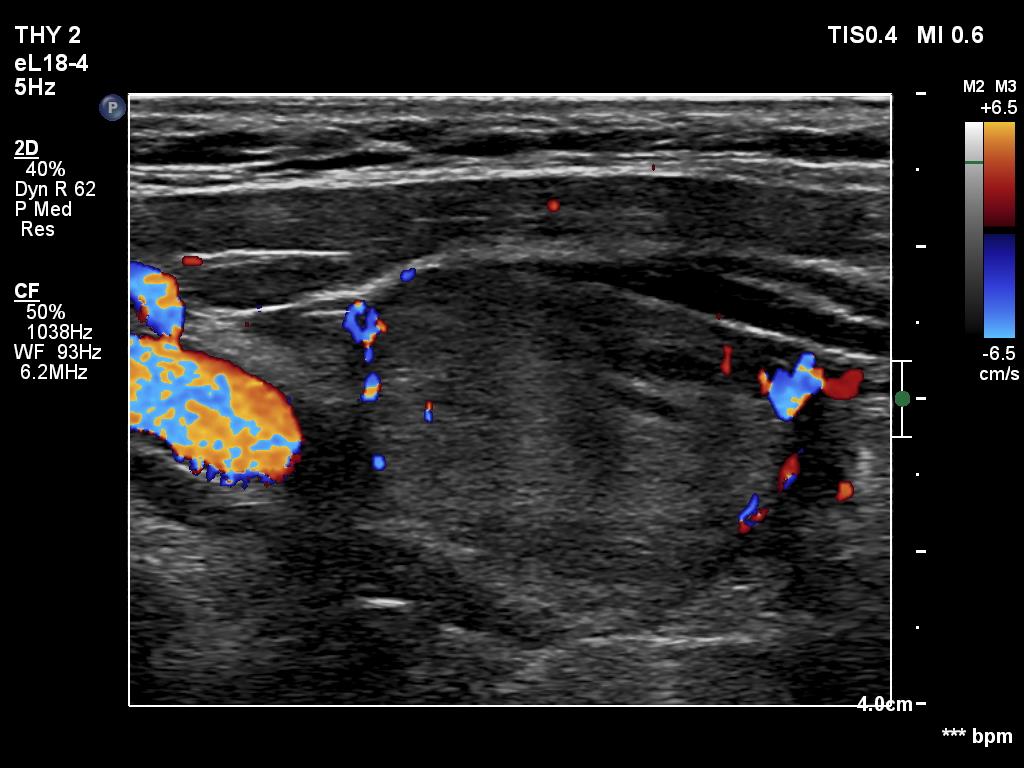

Ultrasonography. The thyroid was hypoechogenic. There was an iso/hyperechoic nodule in both the right and left lobes. The nodule in the left lobe had perinodular vascularity. The dimensions of the nodule in the left lobe were 20x18x31 mm, width, depth, length, respectively. This means that the volume of the nodule has increased almost 8-fold in 10 years.